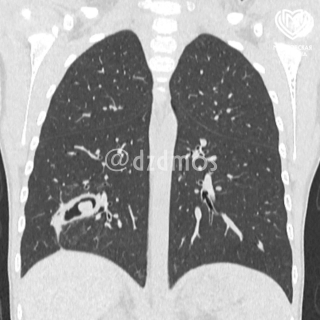

«Врачи провели обследование и на КТ увидели серьезные видоизменения в бронхах. Это было инородное тело в дыхательных путях справа, которое угрожало здоровью девочки. Как выяснилось, часть скорлупы семечки глубоко впаялась в третий субсегмент правого 🫁 легкого, из-за чего у пациентки образовался бронхоэктаз, то есть плохо функционировали из-за скопления гноя бронхи», — рассказал Дмитрий Еремин, детский хирург, заместитель главного врача по хирургической помощи.